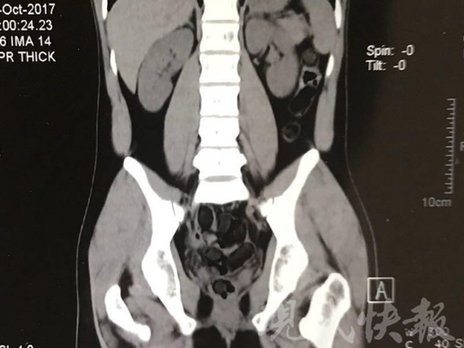

由于毒品在體內(nèi)一旦泄露有可能致命,警方第一時(shí)間將阿永帶到醫(yī)院進(jìn)行檢查。CT 掃描的結(jié)果顯示,阿永體內(nèi)布滿了密密麻麻的白色圓柱狀固體,就像一粒粒的蠶蛹。在南京市公安局鼓樓分局二板橋派出所,阿永分四次排出了毒品,毛重369.99克。經(jīng)訊問,阿永交代了自己全部的犯罪事實(shí)。目前,阿永已被刑事拘留。